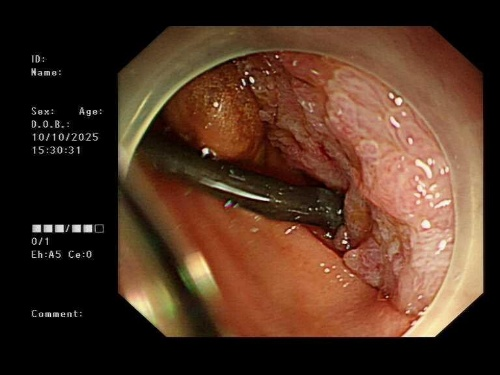

超声内镜探头如同高精度的“GPS导航”,在胃腔内实时扫描,清晰显示出肿瘤的边界、周围血管的搏动,以及最佳“桥墩”定位点。

在超声的实时引导和X光造影的监控下,穿刺、导丝置入、支架释放……

一系列步骤如行云流水。

当那枚双蘑菇头支架在胃与空肠之间成功展开,宛如一朵生命之花在体内绽放,一座避开所有险滩的“人工桥梁”就此贯通。